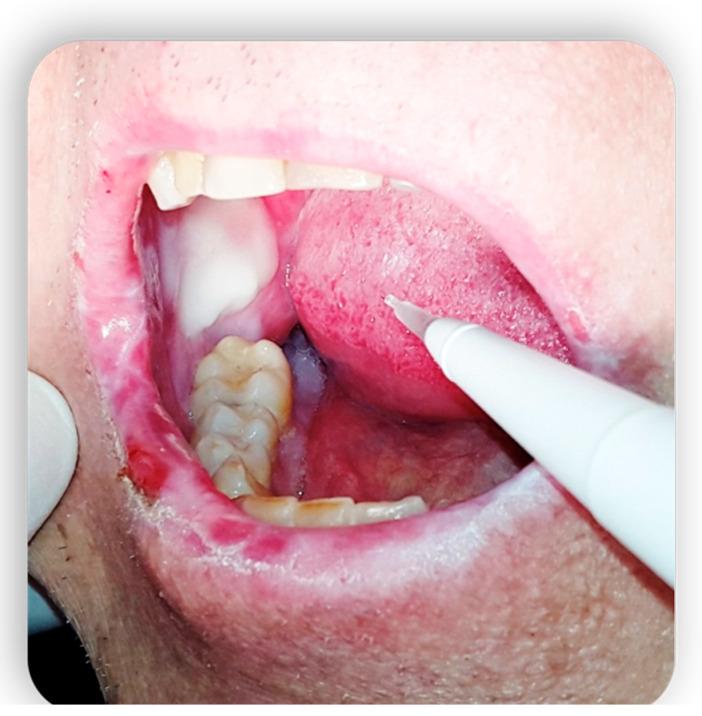

Graft-versus-host disease (GVHD) is a complication of hematopoietic stem cell transplantation (HSCT). GVHD may also develop following solid transplants or blood transfusions if white blood cells are transferred. GVHD affects multiple organs, including the oral tissues. This pictorial review provides a background of GVHD to dental practitioners, describes the most common oral manifestations of GVHD, and highlights the main treatment modifications needed to deliver dental care to patients with GVHD. A narrative review enriched with clinical data was performed by searching the scientific literature for all articles regarding GVHD and oral manifestations/therapies. All articles without exclusion criteria, except animal tests, were included in the above review. Acute GVHD may manifest in the oral mucosa; however, it often develops immediately following HSCT when routine dental treatment is postponed. Chronic GVHD may manifest in the oral mucosa, the salivary glands, and the musculoskeletal compartment. It may indirectly affect the teeth and the oral flora, putting the patient at risk for infections. Importantly, GVHD poses an increased risk for oral cancer. GVHD has a wide range of oral manifestations, some of which may affect dental treatment.